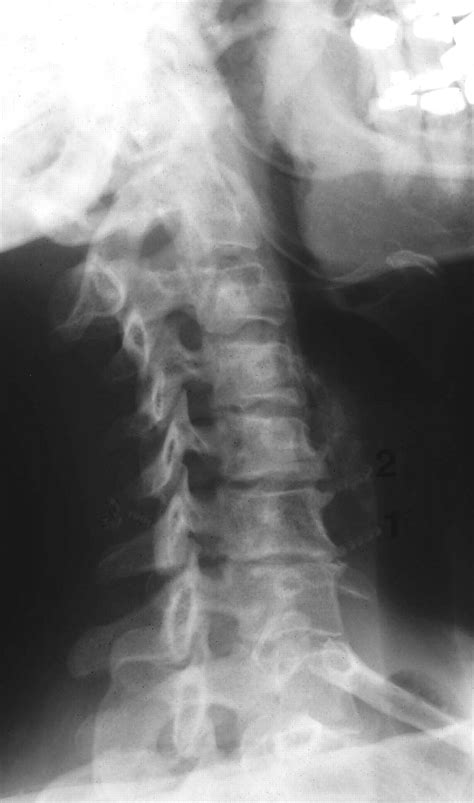

• Imaging Tests: X-rays, MRI, or CT scans to visualize the bones and soft tissues in the neck.